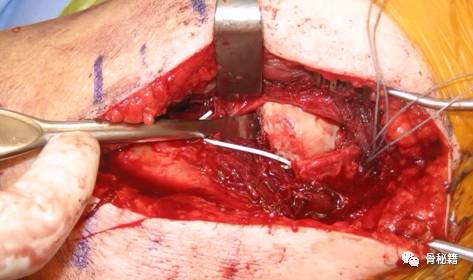

然后就可以进入肱骨近端了,整体暴露图 上方为小结节,下方为大结节。

1、用4843缝线,分别将肩袖、大结节、小结节处进行缝合

2、用骨拨进行头下翘拨复位

3、复位好头之后,将小结节和大结节互相牵拉后闭合头颈部分

4、克氏针临时固定,用钢板压住骨折块